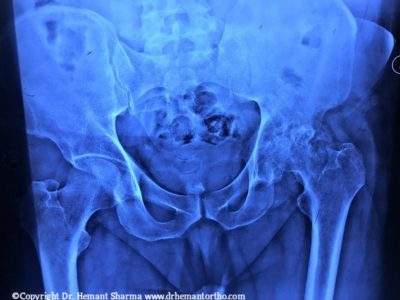

PRE-OPERATIVE